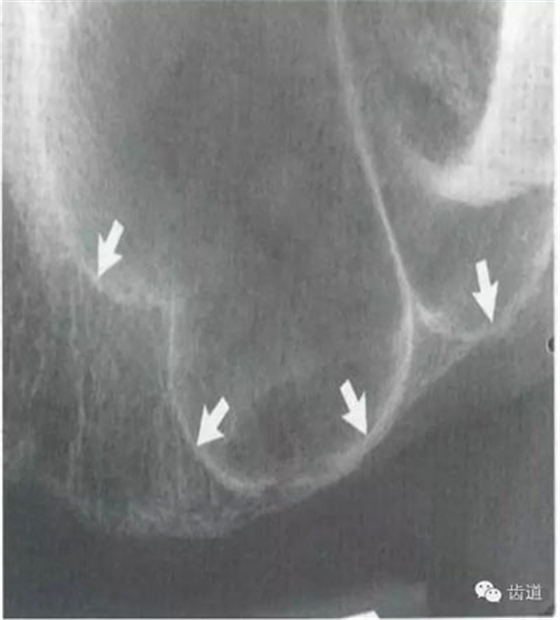

位于磨牙牙根尖下方,呈寬約為0.4cm凹面向下邊緣整齊的帶狀密度低的影像,其兩側(cè)有密度高的線條狀影像,為下頜管骨密質(zhì)

7)下頜角區(qū):

在下頜管的后下區(qū)域,骨小梁稀少,這是正常骨質(zhì)疏松區(qū)域 8)頦嵴: